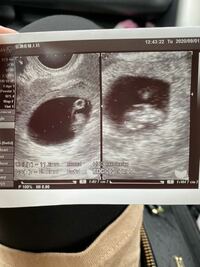

こんにちは、pikaです。2歳の双子男児を育てています。 前回のエピソード: 胎嚢や羊膜の数によってリスクが異なる双子妊娠。NICUのある施設へ転院することに by pika 双子を妊娠中のお話。 今回は、妊娠初期に経験した出血についてのお話です。 妊娠10週 3歳の一卵性双子+第3子妊娠中です。 双子のときは、初診が5週で胎曩が見えました。このときは1つだけ確認でした(今思えば 見落としたのかな)。 翌週、6週後半だったと思いますが、そのときに胎曩が2つ見えて双子と発覚。双子妊娠はいつわかる?一卵性の女の子を出産した私の体験談 一卵性の双子チャンの妊娠について。現在6週目に入ったばかり 二卵性双子のエコー写真5週~29週公開&双子4dエコーの 妊娠3ヶ月(妊娠8週0日~11週6日)の胎児の超音波画像(1) 超

二卵性双子のエコー写真 5週 29週 公開 双子4dエコーの疑問を解決 双子ライフ

妊娠記録2 双子妊娠 7w 9w 母子手帳を貰いに行った 双子だけど つわりはほとんどなく 順調 エコー写真有 ジョイライフ

双子判明 6w Dragontwins